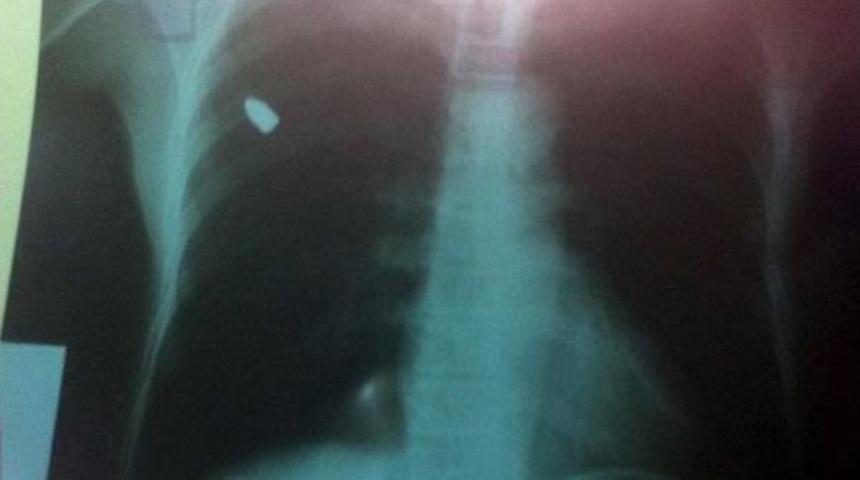

Emrullah KARAKAŞ/DERİK Derik İlçesi'ne bağlı Tepebağı Mahallesi'nde oturan Selahattin Dağlık dün gece evinin avlusunda uyurken göğsünde bir acı hissetti. Yakınları tarafından Derik Devlet Hastenesi'ne götürülen Dağlık, doktorun şikayetini sorması üzerine avluda uyuduğu sırada nereden atıldığı belli olmayan bir taşın göğsüne isabet ettiğini ve göğsünün kanadığını söyledi. Bunun üzerine muayene edilen röntgeni çekilen Dağlık'ın sağ göğsünden giren bir kurşunun akciğerine saplandığı anlaşıldı. Bunun üzerine Mardin Devlet Hastanesi'ne sevk edilen Selahattin Dağlık ameliyata alındı. Dağlık'ın göğsünden girip sırt kısmında kalan kurşun, başarılı bir operasyonla çıkarıldı.